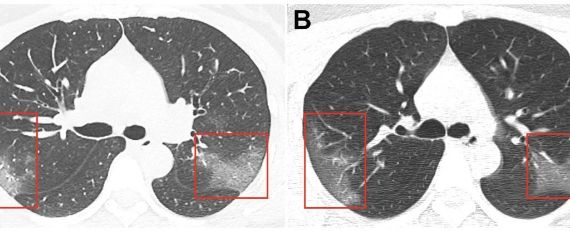

While it’s too early to establish long-term effects of the disease… With scanning a group of 12 current coronavirus, doctors found two to three saw changes in their lung capacity. The CT scans showed white patches similar to “ground glass,” a phenomenon in which fluid builds up in lungs producing patterns similar to frosted glass. The area of the affected lung has been described as ” frosted glass “. this kind of damage was found in all of them. This means that that part of the lung tissues has been completely destroyed and cannot be reused or treated.

Below is an image of the scans which was, taken from one coronavirus patient at different stages, showing the progress of the person’s ” frosted area in the lung ” as his illness progressed.